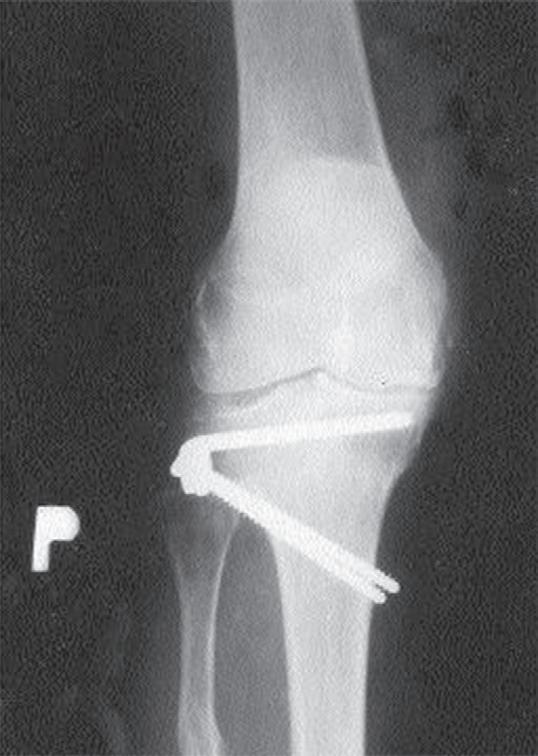

Obr. 19.6: Osteotomie valgizační – otevřená. Provádí se osteotomií z mediální strany proximální tibie a s následným rozevřením fragmentů do tvaru klínu, který koriguje deformitu s následnou fixací osteosyntézou. Předoperační (a) a pooperační rentgenový snímek (b)

Osteotomie má za cíl korekci kloubní osy se změnou zátěžových oblastí kloubu. Operace obnoví osu končetiny a odlehčí tlak na poškozenou oblast kloubu a zmírní tak subjektivní obtíže nemocného. Příznivý výsledek obvykle přetrvává několik let. Dle poruchy osy rozlišujeme osteomie valgizační (korekce genu varum) a varizační (korekce genu valgum). V praxi se provádí klínovitá osteotomie s vytětím kostního klínu, sesazením obou fragmentů a fixací osteosyntézou (tzv. closed wedge osteotomie, obr. 19.5). Druhou možností je provedení jednoduché osteotomie s rozevřením obou fragmentů v klínovitém tvaru a fixace osteosyntézou (tzv. open wedge osteotomie, obr. 19.6). Dále podle anatomické lokality osteotomie rozlišujeme osteotomie distálního femuru (obr. 19.7) nebo proximální tibie. Artrodéza (ztužení kloubu) se primárně používá ve výjimečných případech (obr. 19.8). Je však možným řešením zejména po selhání aloplastiky, pokud není možná implantace nové náhrady. Vzhledem k faktu, že ztužení kloubu probíhá obvykle v terénu rozsáhlých kostních ztrát, používá se v poslední době ztužení kloubu pomocí implantátů – tzv. fúze kolenního kloubu (obr. 19.9). Nejde tedy v pravém slova smyslu o klasickou artrodézu – tedy kompletní primární kostní srůst femuru a tibie.